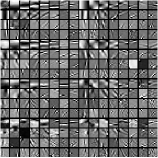

Fig. 1 shows example transforms (rows of are reshaped as patches and the first slices of such 3D patches are shown) learned from patches of an XCAT phantom [54] volume. The transform learned with in (P0) has more oriented features whereas the transform learned with shows more gradient (or finite-difference) type features (pointed by the green arrows). This behavior suggests that a single ST may not be rich enough to capture the diverse features, edges, and other properties of CT volumes. Therefore, next we consider the extension of the ST approach to a rich union of learned transforms scheme.